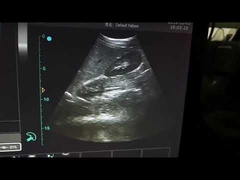

Calidad Escáner de ultrasonido portátil, analizador del ultrasonido del PDA Fabricante de China

Ultrasound scanner